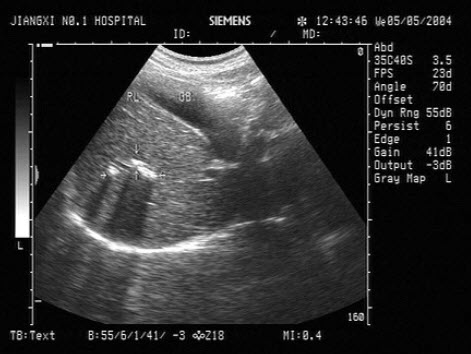

21、单项选择题

超声检查如图所示,该病例最可能诊断()